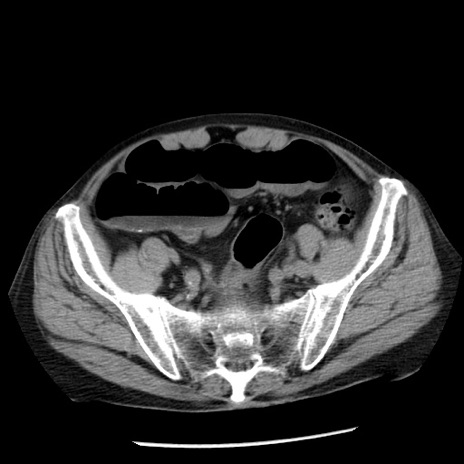

冠状断像

【症例】80歳代男性

【主訴】嘔吐

【現病歴】昨晩2回嘔吐あり、今朝になっても嘔吐あり。来院。

【既往歴】胃潰瘍

【身体所見】意識清明、BT 37.6℃、BP 166/95mmHg、HR 100bpm、SpO2 97%、腹部:平坦・軟、腸蠕動音聴取良好、圧痛なし。

【データ】WBC 21900、CRP 1.46